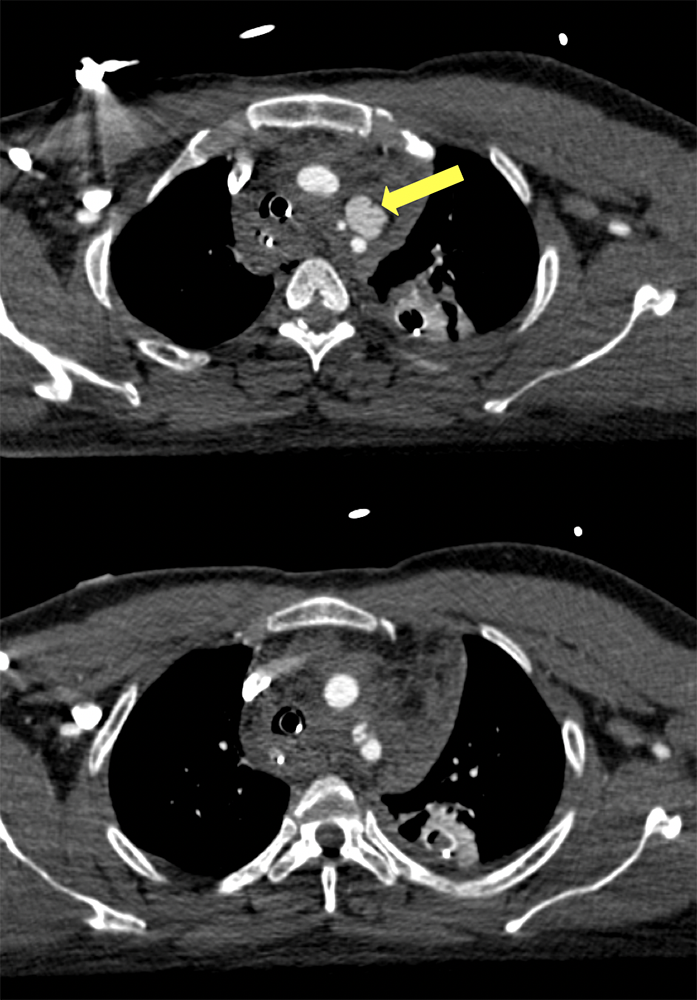

”The best way to distinguish a true aortic root injury from motion artifact is to repeat thoracic imaging with ECG gating; and echocardiography can be a reasonable alternative. The difference between a study done without and with ECG gating is illustrated in. In our institution all of the chest CT done as part of a trauma survey are acquired without ECG gating. Since the majority of TAIs are at the aortic isthmus, which is typically well seen on non-gated studies, we feel the additional radiation exposure and time required for setup and acquisition of an ECG gated study is not necessary for every patient.” Traumatic aortic injury: CT findings, mimics, and therapeutic options Ethany L. Cullen et al. Cardiovasc Diagn Ther 2014;4(3):238-244 |

“A number of artifacts can mimic a traumatic injury of the thoracic aorta. The classic example is that of the cardiac pulsation artifact, especially in the ascending aorta. If there is any doubt, CT angiography with ECG-gating or a transoesophageal echocardiogram will allow this pathology to be excluded in stable patient. Nonetheless, there remain a number of pitfalls that require particular attention.” Traumatic injuries of the thoracic aorta: The role of imaging in diagnosis and treatment F.Z. Mokranea et al. Diagnostic and Interventional Imaging (2015) 96, 693—706 |